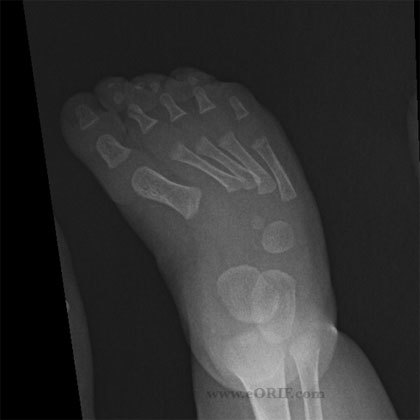

Club Foot (talipes equinovarus)

M>F, 50% bilateral

4 components: hindfoot varus, calcaneus equinus *(en pointe), metatarsus adductus, and talonavicular subluxation